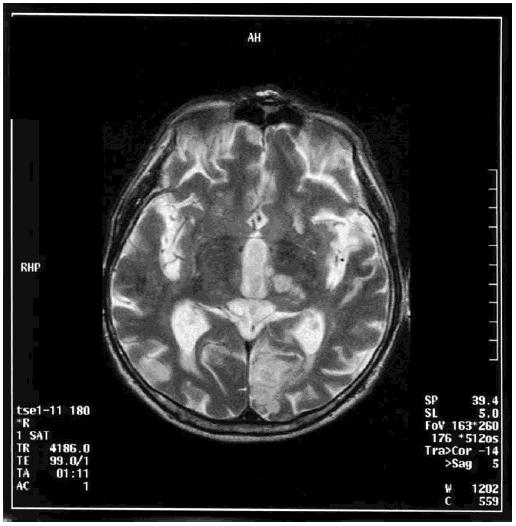

Анализ состояния когнитивных функций, проведенный у 450 пациентов в возрасте старше 65 лет через пять лет после госпитализации по поводу инфаркта головного мозга, выявил клинические проявления сосудистой деменции у 14 % обследованных больных [223]. Сосудистая деменция ассоциировалась с вовлечением в патологический процесс средней мозговой артерии, нейровизуализационными данными (лейкоареоз, множественные ишемические повреждения, кортикальные очаги), наличием сахарного диабета, атриальных фибрилляций, дисфазии, нарушением походки. Такие показатели, как старший возраст и низкий уровень образования, имели независимую корреляционную связь с наличием сосудистой деменции. У обследованных пациентов преобладал церебральный тромбоз (68 %), в 22 % выявлялась внутримозговая геморрагия, у 9 % – субарахноидальное кровоизлияние. Следовательно, развитие сосудистой деменции, которое в большинстве случаев связано с гипоперфузией определенных областей головного мозга, часто происходит в исходе ишемического или геморрагического инсультов. На рис. 6.1 представлена МРТ головного мозга пациента с сосудистой деменцией, развившейся после повторных ишемических инсультов.

Иллюстрация к книге — Деменция. Диагностика и лечение [i_004.jpg]

Рис. 6.1. МРТ головного мозга пациента с сосудистой деменцией